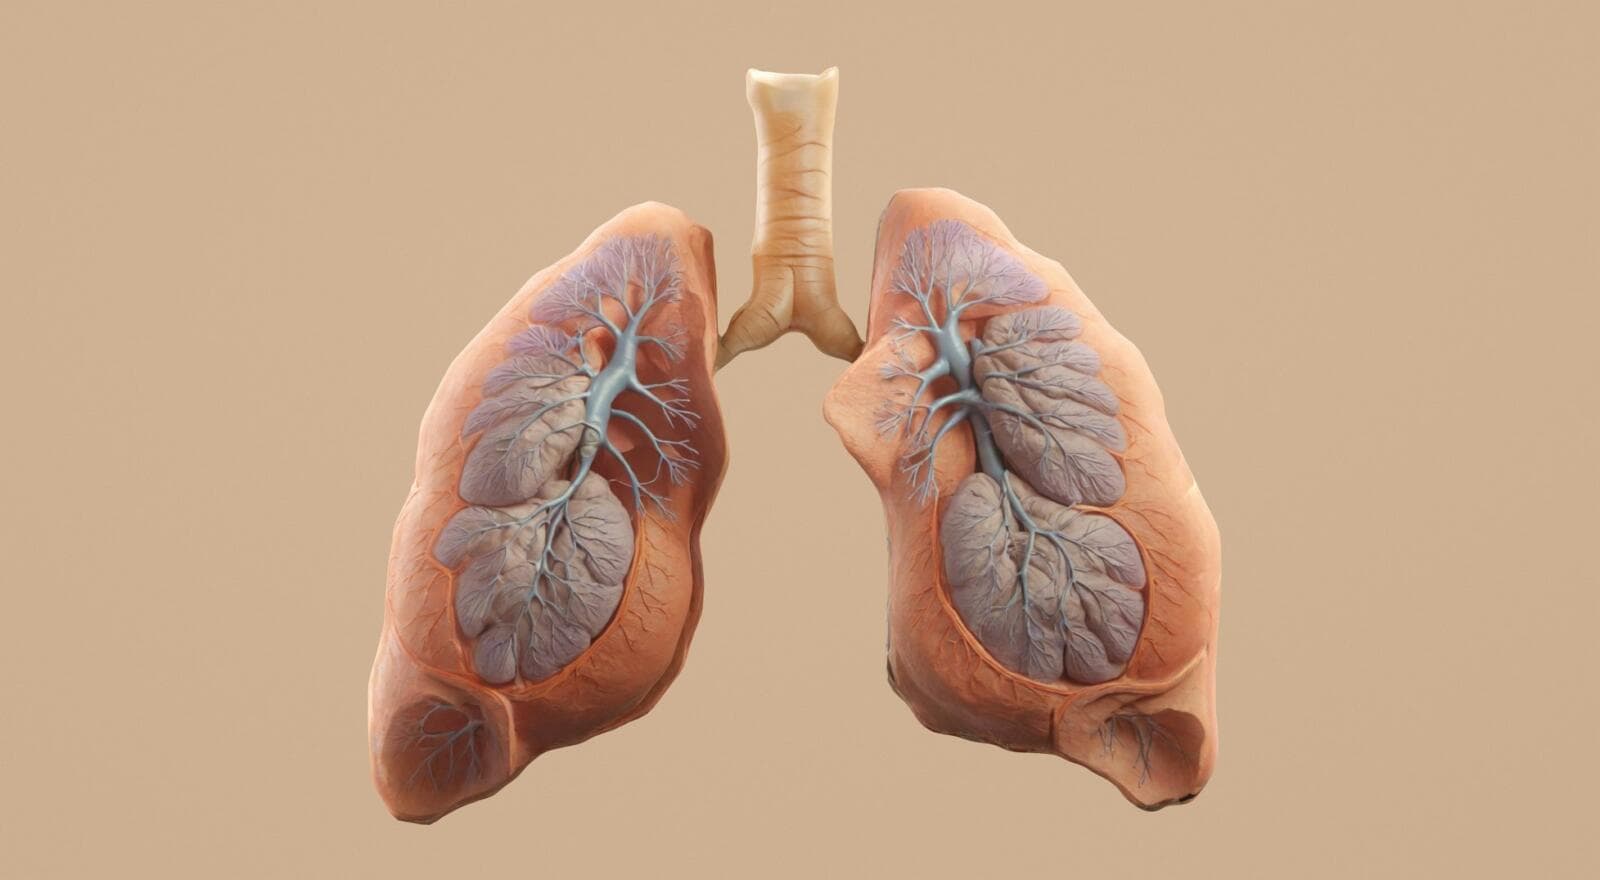

How Aēir™ Is Reimagining the Asthma Spacer - and Protecting the Idea from Day One

Asthma doesn’t always arrive at a convenient moment. It might be on a school run, mid-commute, on a walk, or halfway through a busy day - the kinds of situations where you’re...